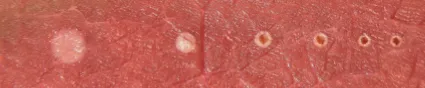

Es una intervención relativamente sencilla, que se realiza con sedación y no deja cicatriz. Una vez anestesiado el paciente y retirada la membrana timpánica se accede al oído medio, donde el cirujano extrae el estribo y lo sustituye por una prótesis que queda fijada en la pletina del oído. Hasta ahora esta prótesis se fijaba abriendo unos orificios en la pletina con la ayuda de una fresa eléctrica o un láser de CO2. Ahora, el nuevo láser azul, con una longitud de onda de 445nm, permite una mayor precisión y control en el tejido gracias a su alto nivel de coagulación y vaporización.

El láser azul es un tipo de láser de microchip que tiene una longitud de onda de 445nm lo que lo convierte en el láser con mayor poder de absorción de hemoglobina en el mercado. Este alto poder de absorción hace que sea un láser muy controlable, con gran capacidad fotoangiolítica y de corte sin necesidad de contacto con el tejido. Esta característica es muy importante a la hora de trabajar en campos quirúrgicos muy reducidos como es el caso del oído, ya que reduce el sangrado y favorece la buena visibilidad del cirujano.

Además el láser azul produce menos calor que los láseres tradicionales utilizados en este campo, lo que hace que el daño a tejidos cercanos sea menor y acelera la recuperación del paciente.

[/vc_column_text][vc_column_text]El láser azul trabaja con fibras de 300, 400 y 600 micras que actúan coagulando o vaporizando en función de la potencia, duración de pulso y distancia con el tejido. La curva de aprendizaje es mínima y el efecto es más eficaz que el producido por láseres convencionales como el de CO2.wf